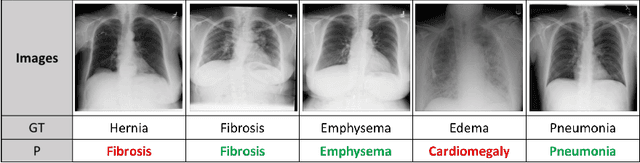

Abstract:Due to the scarcity of annotated data in the medical domain, few-shot learning may be useful for medical image analysis tasks. We design a few-shot learning method using an ensemble of random subspaces for the diagnosis of chest x-rays (CXRs). Our design is computationally efficient and almost 1.8 times faster than method that uses the popular truncated singular value decomposition (t-SVD) for subspace decomposition. The proposed method is trained by minimizing a novel loss function that helps create well-separated clusters of training data in discriminative subspaces. As a result, minimizing the loss maximizes the distance between the subspaces, making them discriminative and assisting in better classification. Experiments on large-scale publicly available CXR datasets yield promising results. Code for the project will be available at https://github.com/Few-shot-Learning-on-chest-x-ray/fsl_subspace.